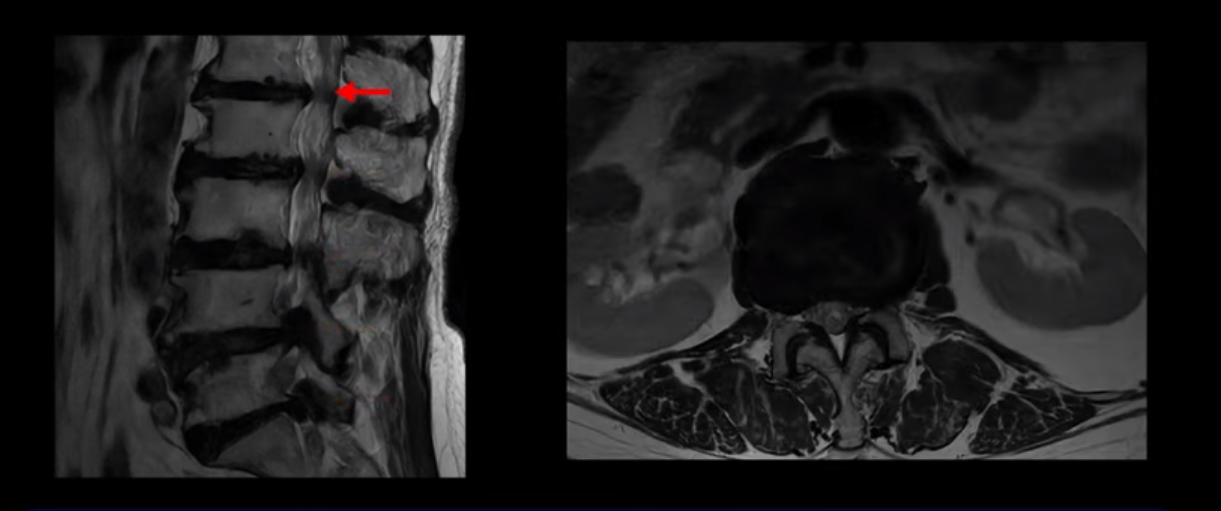

이 환자분은 MRI로 보면 허리 여러 마디가 신경이 매우 심하게 눌려 보이는 분입니다. 이분 MRI를 보면서 간단히 설명해 드린 후 어떻게 이렇게 신경이 심하게 눌린 환자분이 수술 없이 근육신경재활치료로 좋아질 수 있는지, 다리가 아파 걷지 못하는 환자가 어떻게 안 아프고 잘 걸을 수 있게 되는지, 10년 동안 괴로웠던 양 발의 시린 증상은 어떻게 사라질 수 있는지, 치료는 어떻게 하는지 자세히 설명 드리겠습니다.

MRI 보시면 (2-8) 허리의 5마디가 전부 다 심하게 퇴행되어 있습니다.

5마디 전부 다 심한 중심성 협착이 있습니다.

1번 2번,

이렇게 모두 다 심하게 막히는 경우는 드문데요. 또한 오른쪽, 왼쪽 신경이 빠져나가는 추간공도 다 심하게 막혀있습니다.

오른쪽, 왼쪽 이렇게 신경 구멍들이 다 좁아지고 신경이 눌리니까 양쪽 다리가 발바닥까지 아파서 걷기 어렵고 양쪽 발이 10년 넘게 시린 겁니다. 당연히 수술해서 눌린 신경을 풀어줘야 한다고 들으셨는데요. 이런 환자분을 어떻게 수술 없이 치료할까요? 지금부터 설명해 드립니다.

이분 신경이 눌리는 증상은 오래됐지만, 증상이 아주 심해진 건 올해 들어와서입니다. 그럼, 이분 MRI 영상도 이렇게 심하게 안 좋아진 게 올해 들어와서일까요? 이분의 MRI로 보이는 협착은 아주 오래된 겁니다. 그래서 신경 구멍이 심하게 좁아진 것도 올해가 아니고 오래된 겁니다. 작년, 재작년에 훨씬 덜 아팠을 때 MRI를 찍었어도 신경 구멍 좁은 정도는 별반 차이가 없었을 겁니다.